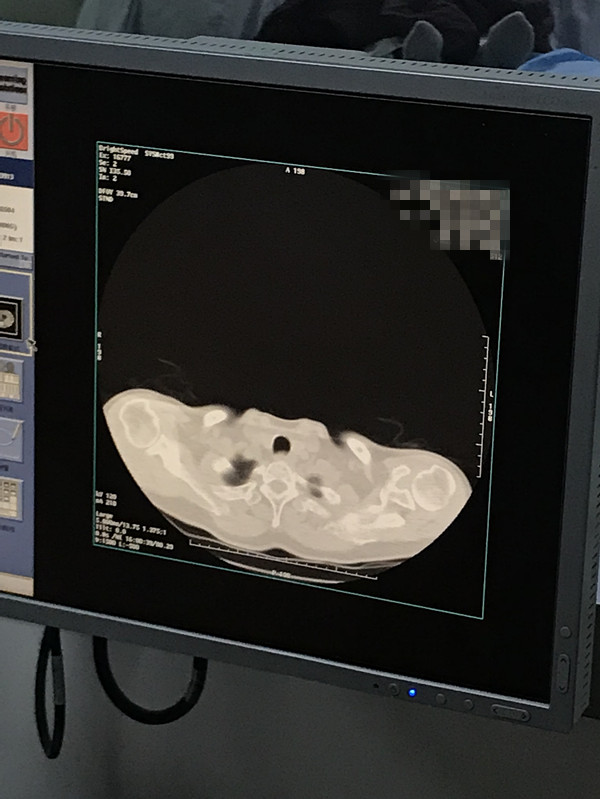

下一篇:2021年1月份肺部氩氦刀手术